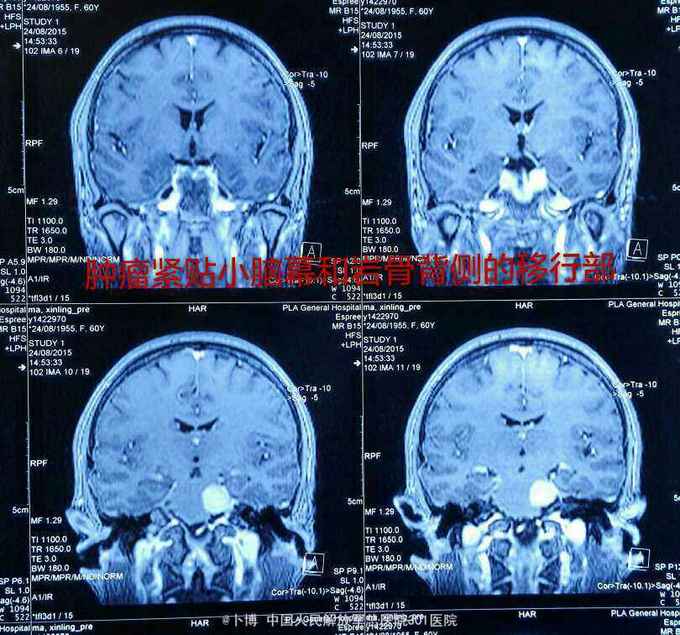

诊断:左侧岩斜脑膜瘤。 手术:乙状窦后入路。肿瘤位于面听神经的前方,将三叉神经根推向内侧。为了扩大显露并彻底切除肿瘤(基底),磨除了部分道上结节的骨质。 肿瘤全切。面听神经及三叉神经保留。